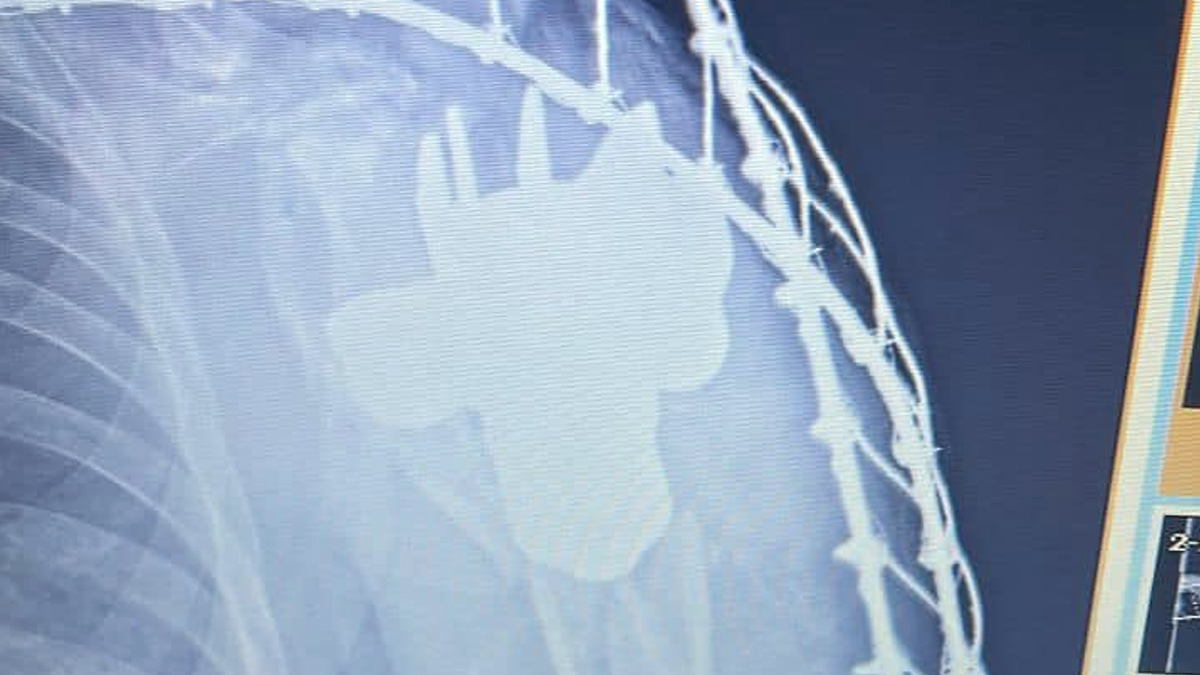

Військові лікарі дістали хвостовик міни з тіла військовослужбовця

Українські військові лікарі дістали хвостовик міни з тіла військового.

«При дообстеженні лікарями одного з прифронтових шпиталів у тілі пораненого було виявлено сторонній предмет, контури якого нагадували хвостовик міни. На місце було викликано бригаду саперів, які після дослідження засвідчили, що сторонній предмет можна видалити безпечно. Після дослідження лікарі було ухвалили рішення про оперативне втручання та видалення хвостовика», — йдеться у повідомленні.

Наразі самопочуття пацієнта — стабільне. Фахівці Медичних сил готують його до подальшої медичної евакуації та реабілітації.